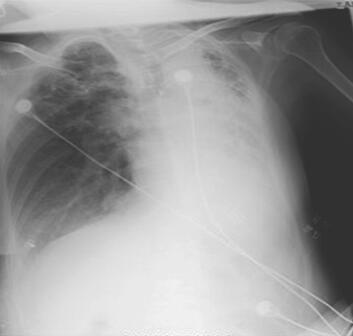

辅助检查:血常规:WBC 7.98×109/L,Hb 130g/L,PLT 173×109/L,N 75.4%。凝血:PT 14.6秒,APTT 28.7秒,Fbg 2.75mg/dl,D-二聚体364μg/L。胸片见图1,胸部CTA见图2。超声心动图示心房增大,肺动脉高压,PASP 51mmHg,主动脉硬化、瓣膜钙化并狭窄及反流,三尖瓣中重度关闭不全、左心室收缩功能正常。腹部B超示肝静脉及下腔静脉增宽,注意排除右心功能不全可能;门静脉主干增宽,未见血栓;肝周少量积液。

图1 胸片示左肺不张或硬变,纵隔左移,肺内结构观察欠清;右上肺纤维增殖性结核灶;右下肺纹理稍增多、模糊,考虑少许支气管周围炎